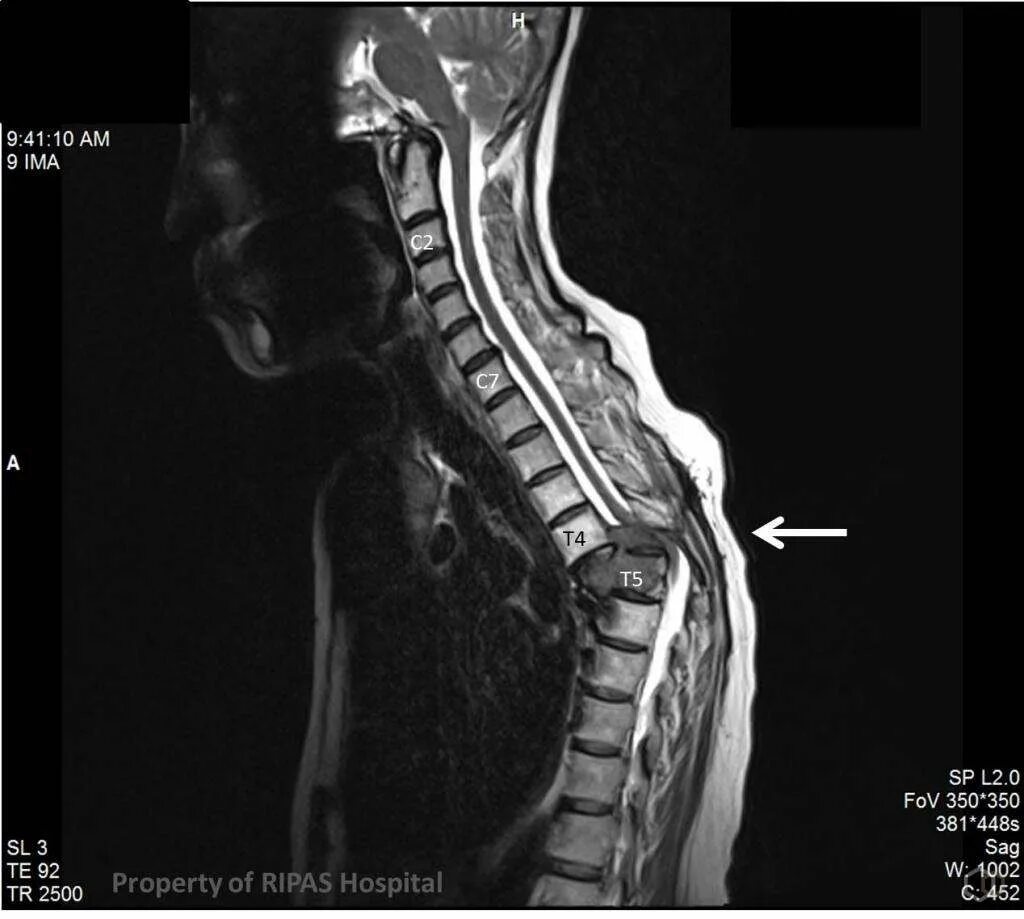

Перелом грудного позвонка код